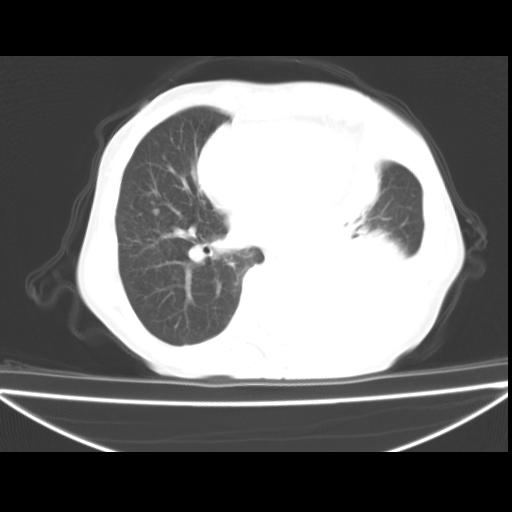

以下是引用zxl51642在2010-3-24 18:49:00的发言:[br]结合乳腺癌术后病史,考虑双肺及纵隔淋巴结多发转移、左侧胸膜转移并左侧大量胸水、左下肺膨胀不全。